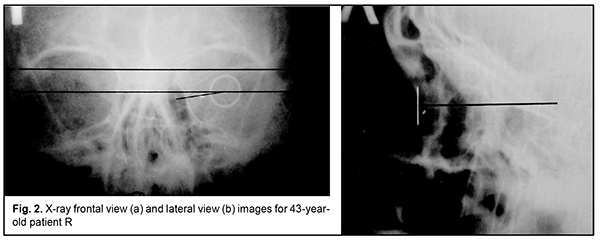

Introduction Ocular trauma is still a leading cause of loss of vision and legal blindness and vision impairment. Intraocular foreign bodies (IOFBs; such as metal, glass, rock, etc.) are seen in 15%-40% of penetrating ocular injuries [1, 2]. IOFBs sized 1-2 mm are most common and can cause early and late complications (endophthalmitis, metallosis, etc.) which are more significant in terms of their effect on health than the trauma caused by such a body itself. IOFBs sized more than 5 mm commonly cause significant damage to the eye, and may lead to loss of not only vision, but also of the whole eye. Accurate IOFB localization is essential for the success of IOFB removal. Until recently, orbit X-ray in two views using the Comberg-Baltin prosthesis was the primary imaging modality for localizing radiopaque IOFBs. Although other modalities can be used today for localizing radiopaque IOFBs, they do have certain diagnostic disadvantages. Because the X-ray method of foreign body localization is widely available, cost-effective, and offers sufficient accuracy for surgical planning, it is still relevant. It is used in combination with contemporary imaging modalities (CT, ultrasound, etc.) and, if these are unavailable, it can be used as the primary imaging modality. Although the ultrasound method is, undoubtedly, of value in localizing IOFBs, especially radiopaque ones, it cannot localize the IOFB accurately enough to remove the latter immediately. In addition, it is effective only if combined with the X-ray method. Computed tomography (CT) scan provides more differentiated images of ocular tissue and media, and can identify IOFB and precisely locate it with respect to the adjacent ocular structures in most cases. CT is the indispensable imaging examination technique in the presence of numerous IOFBs, but is not always effective in determining IOFB size and shape. In CT scans, a foreign body sized less than 3 mm appears as a regular round body, and that sized 3 to 7 mm appears as an irregularly round or oval-shaped body, although the actual size and shape may differ from those seen in the CT. CT images of metal IOFBs often suffer from bright and dark streak artifacts that radiate from the shadow of metal IOFB. If there is any possibility that the foreign body may be metallic, magnetic resonance imaging (MRI) should not be performed because of possible movement of the object and consequent damage to intraocular structures. Scleral subconjunctival hemorrhage is more commonly caused by larger IOFBs. In addition, hypertrophy of the scleral conjunctiva surrounding the limbus may arise from other causes such as allergic response, burns, consequences of severe concussion, etc. Marking the position at the limbus presents some difficulties in the presence of apparent chemosis or scleral subconjunctival hemorrhage. As it is difficult or impossible to make the Baltin prosthesis adjacent to the limbus under these circumstances, other methods have been proposed for marking the position at the limbus. Baltin [3] proposed to apply bismuth pulp to mark the limbus at 6 and 12 o’clock axes with a (preferably plastic) probe when the lids are separated with eye speculum. Bismuth pulp spreads over the eye and is washed away by tears rather frequently. In addition, the eye must be kept immobile during examination, which is almost impossible. Vodovozov [4] proposed to mix bismuth or barium sulfate with nitro-glue or collodion, make small silver-paper half-discs and soak them in this mixture, and use them to mark the limbus. These adhere well to the limbus, are not washed away by tears, and exhibit no displacement during movements of the eye. Poliak [5-6] proposed to introduce T-shaped studs beneath the conjunctiva at the limbus at 3 and 9 o’clock axes. Adhering, suturing or fastening various radiopaque markers at the limbus causes incongruous shadows on X-ray films, and can result in increased damage to the eye. Because radiopaque objects are placed by sight and hands and in one plane, approximately at certain meridians, location of the IOFB in the eye is estimated with a significant error. Marking the center of the cornea with a probe, dressing forceps, or other methods (Plittas, 1941; Bogatin, 1949; Madroszkiewiz, 1954, etc) have not been widely implemented due to their small effect [7]. A limbal ring (internal diameter, 12 mm) made of 1-mm thick wire, which is sutured or adhered to the conjunctival sclera, cannot mark the limbus in cases of hypertrophy of the scleral conjunctiva, and it is difficult or impossible to make the ring adjacent to the limbus. In addition, it should not be used in the presence of fresh, gaping wound [8-10]. Gardona and Trokel [11] used a soft vacuum lens for X-ray localization of foreign bodies in eyes with maintained corneal sphericity. Such a lens remains well secured and does not change its position over the cornea, which facilitates adequate localization of the IOFB. Taking into account the relevance of the problem, we have been looking for a new way to solve it. We made a corneal prosthesis (limbus marker; Innovation Proposal No. 556/54 dated 12.07.1989), which is a rigid corneal contact lens (optical power, 0D; diameter, 11 mm; thickness, 0.3-0.35) made of polymethylmethacrylate. The lens has 0.5-mm lead marks in four quadrants (3, 6, 9 and 12 o’clock); lead mark edges and lens edges coincide with each other. The distance between external contours of adjacent marks is 11 mm, and the distance between internal contours is 10 mm. The prosthesis is well fit in the specified position over the cornea during X-ray examination. It can be used if the conjunctiva and lens are abnormally spherical in shape (chemosis and/or subconjunctival hemorrhage) and in the presence of a fresh scleral wound. The purpose of the study was to improve the accuracy of X-ray localization of foreign bodies in the presence of apparent chemosis or scleral subconjunctival hemorrhage through the use of the ring-shaped limbus marker. Material and Methods We proposed a method for marking the limbus during X-ray localization of foreign bodies in the presence of apparent chemosis or scleral subconjunctival hemorrhage through the use of the ring-shaped limbus marker (Patent of Ukraine No. 12,015 issued 25.10.2017; Bulletin No. 20). The ring is made from 0.5-0.7-mm stainless steel wire. Rings with external diameters of 10, 11 and 12 mm were made for examining eyes of different sizes. The examination procedure was as follows. After epibulbar anesthesia, a sterile ring-shaped limbus marker of the appropriate size was placed on the cornea against the limbus. It was well fit in the specified position due to hypertrophy of the conjunctiva surrounding the cornea, and corresponded to the conjunctival attachment to the limbus. The posterior-to-anterior (frontal view) orbit X-ray was taken as per the technique described by Itsykson (using the grating), which allowed for control of the eye and limbus marker for correct position during roentgenography. In lateral or axial view, the shadow of ring-shaped limbus marker appeared as a straight line, and in a PA view, it appeared as a ring. Orbit X-ray was performed, quality of X-ray films was assessed and IOFB position in the eye was calculated using the technique of Comberg-Baltin or Abalikhin-Pivovarov. In order to determine the projection of the anteroposterior axis of the eye, the measurement scheme was put on the PA X-ray film so to get the limbus marker shadow inside the relevant circle of the scheme. Thereafter, the needle was used to puncture the PA X-ray film through the measurement scheme and at the intersection of horizontal and vertical meridians. This puncture point at the X-ray film corresponded to the projection of the antero-posterior axis of the eye. Ring-shaped limbus markers with external diameters of 11 and 12 mm were utilized in 10 cases and 2 cases, respectively, in the presence of limbal conjunctival hypertrophy. Results In 12 patients, IOFB was successfully removed based on the data obtained from X-ray localization by means of the ring-shaped limbus marker. In two patients without limbal conjunctival hypertrophy, foreign body X-ray (PA view and lateral view) localization was performed by means of the Baltin’s prosthesis. Thereafter, these two received a paralimbal subconjunctival injection of 0.9% NaCl, and foreign body X-ray localization was performed by means of the ring-shaped limbus marker. Calculations for X-ray (PA view) localization by means of the Baltin’s prosthesis were in agreement with those for X-ray (PA view) localization by means of the ring-shaped limbus marker. In addition, with regard to the X-ray lateral view and X-ray axial view, the position of the IOFB relative to the ring-shaped limbus marker was 1 mm deeper than that relative to the Baltin’s prosthesis due to the location of the limbal circle in the eye. Figs 2 and 3 present X-ray films (frontal projection, a; and lateral projection, b) of the orbit and ring-shaped limbus marker taken on two patients. Example Case 1 A 43-year-old man sustained injuries from a battery explosion. At admission to the trauma centre, he was diagnosed with Poliak grade 1-2 chemical (battery acid) burn to face, conjunctiva and cornea, and a suspected foreign body in the left eye. OD: His right eye was normal. OS: His uncorrected visual acuity in the left eye was 0.1. There was photophobia and subconjunctival hemorrhage, and the bulbar conjunctivae showed a marked collar of edema at the limbus. A 2-3-mm conjunctival wound was found 5 mm from the limbus at the 8 o’clock meridian. The left eye showed subtotal corneal erosion and edema. The left anterior chamber was of moderate depth. The pupil was round and reactive to light. A pink fundus reflex was observed. Fundus structures were poorly seen. The intraocular pressure (IOP) was normal. A shadow of metal IOFB measuring 1х1х2 mm was seen in X-ray films (frontal projection and lateral projection) of the orbit and limbal circle. In the frontal view of orbital X-ray with the ring-shaped limbus marker, the IOFB was seen along the 8:40 o’clock meridian, 9-11 cm from the sagittal axis of the eye, and 1.5-3 mm beneath the horizontal meridian of the eye. In the lateral view of orbital X-ray with the ring-shaped limbus marker, the IOFB was seen 1.5-4 mm posterior to the conjunctival attachment to the limbus, and 1.5-3 mm beneath the horizontal meridian of the eye. The sagittal axis of the eye was 24 mm long. That is, the IOFB was along the 8:40 o’clock meridian, 1.5-4 mm posterior to the conjunctival attachment to the limbus, and 9-11 mm from the sagittal axis of the eye, i.e., within the scleral subconjunctival hemorrhage region. Example Case 2 A 44-year-old man sustained a left-eye injury due to a power lawnmower. At admission, he was diagnosed with the penetrating sclera wound, vitreous hemorrhage and IOFB in the left eye. OD: His right eye was normal. OS: Visual acuity was light perception with inaccurate projection of rays OS. The corneal and sclera wound was linear and vertical, 9-10 mm in length at 2 mm from the limbus at the 3 o’clock meridian; it was seen between 4-5 mm above and 4-5 mm beneath the horizontal meridian. There was scleral subconjunctival hemorrhage around the limbus. The anterior chamber was filled with blood. The IOP estimated by palpation was significantly decreased. In the frontal view and lateral view of orbital X-ray with the ring-shaped limbus marker, the shadow of IOFB measuring 4х7.5х21 mm was seen in the inferior lateral quadrant of the orbit, 3-20 mm from the sagittal axis of the eye, and 20-30 mm posterior to the conjunctival attachment to the limbus, i.e., within the posterior pole wound. In addition, a 2-3-mm portion of the IOFB was situated in the vitreous, and the rest portion extended beyond the eye to the orbit.